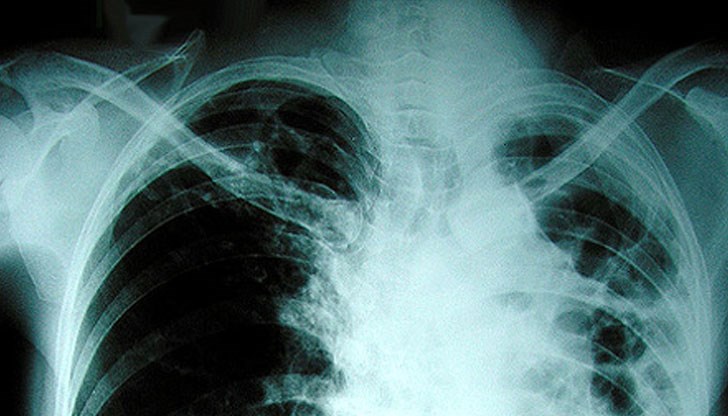

Безплатни прегледи за туберкулоза започват от утре и ще продължат до 23 юни, съобщиха от в Специализираната болница за активно лечение на пневмофтизиатрични заболявания „Д-р Димитър Граматиков“ в Русе.

През цялата седмица ще се провеждат Дни на Отворените врати, в които на всеки желаещ русенец ще се предлага скрининг за риска от туберкулоза. Предварително обаче ще бъде попълнена анкета и ще се премине през консултация с лекар. На съмнителните за туберкулоза лица се извършват прегледи и допълнителни медицински изследвания.

Дните на Отворени врати са ежегодна проява, която стартира през 2009 г. По време на проведените „дни” в периода от 2009 г. до март 2017 г. броят на анкетираните за туберкулоза лица в страната е 93 509, като бяха открити 1039 болни с туберкулоза и 3650 с латентна туберкулозна инфекция. Данните сочат, че се постига добра разкриваемост на случаите на туберкулоза и латентна туберкулозна инфекция.

По време на проведените през месец март 2017 г. „Дни на Отворени врати” в страната броят на анкетираните за туберкулоза лица е 3392, от тях 37 лица са открити с туберкулоза и насочени своевременно за лечение, а 189 са били с латентна туберкулозна инфекция и са обхванати с химиопрофилактика.